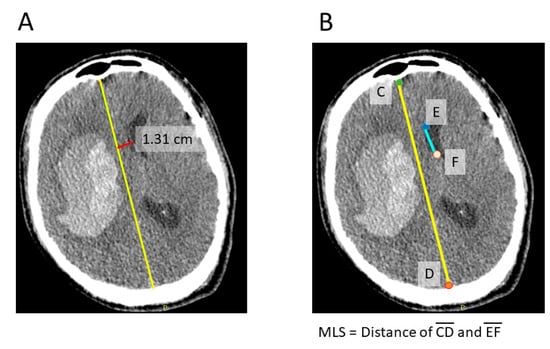

The distance of the midline shift was assessed by using different methods (Figure 1), including manual drawing (Figure 1A), manual keypoint calculation (Figure 1B), and automatic MLS calculation (Figure 2). Manual drawing of the MLS was based on the distance between the falx and septum pellucidum in the most affected CT slice (Figure 1A). All CT scans were manually drawn by three authors (J.-L. Yan, K. Li, B.-A. Chen.) and were blinded to each other’s results. The keypoint for the calculation of the MLS was defined as the anterior end of the falx, the posterior end of the falx, the anterior end of the septum pellucidum near anterior commissure, and the posterior end of the septum pellucidum (Figure 1B). The keypoint MLS was defined as the distance between the middle point of the connection of the anterior and posterior falx and the midpoint of the septum pellucidum.

Figure 1.

Figure 1 shows the method for manually drawing the midline shift (A). Firstly. identify the midline of the brain (yellow line), then measure the distance perpendicular to the septum pellucidum (red line). The manually selected keypoints were defined as shown in (B), including the anterior-most point of the anterior falx (C), the posterior-most point of the posterior falx (D), and the endpoints of the septum pellucidum (E,F). The MLS was calculated by measuring the distance between the middle point of line AD and line BC.